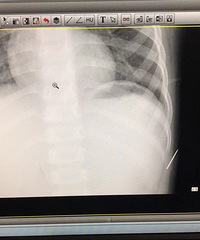

富阳一男孩天天喊“肚子痛”,拍片发现体内竟然有根针!